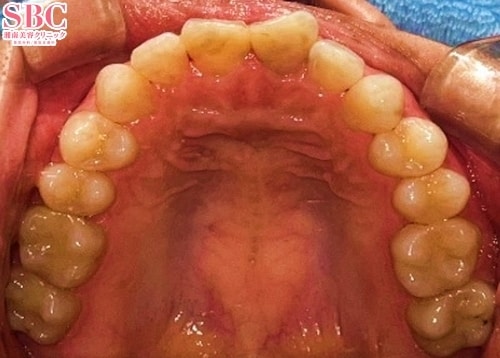

北川哲太郎(歯科) 医師

施術前

施術後6ヶ月後

千葉にくる価値あり!仕上がりの美しさで選ばれてます!自分ではどうにもならない歯の悩みを経験豊富な北川歯科医師が解消致します!お顔全体のバランスを大事にしながら、貴方にピッタリの歯並びをご提案!美容歯科医歴約10年の圧倒的症例数★細やかな施術と綺麗な仕上がりで指名多数!お客様のご希望と、長年培ってきた豊富な知識と経験、技術を掛け合わせて一緒にお悩みを解決致します。丁寧なカウンセリングとスムーズな施術も人気です。まずは、お悩みを聞かせて下さい。ご予約お待ちしています。